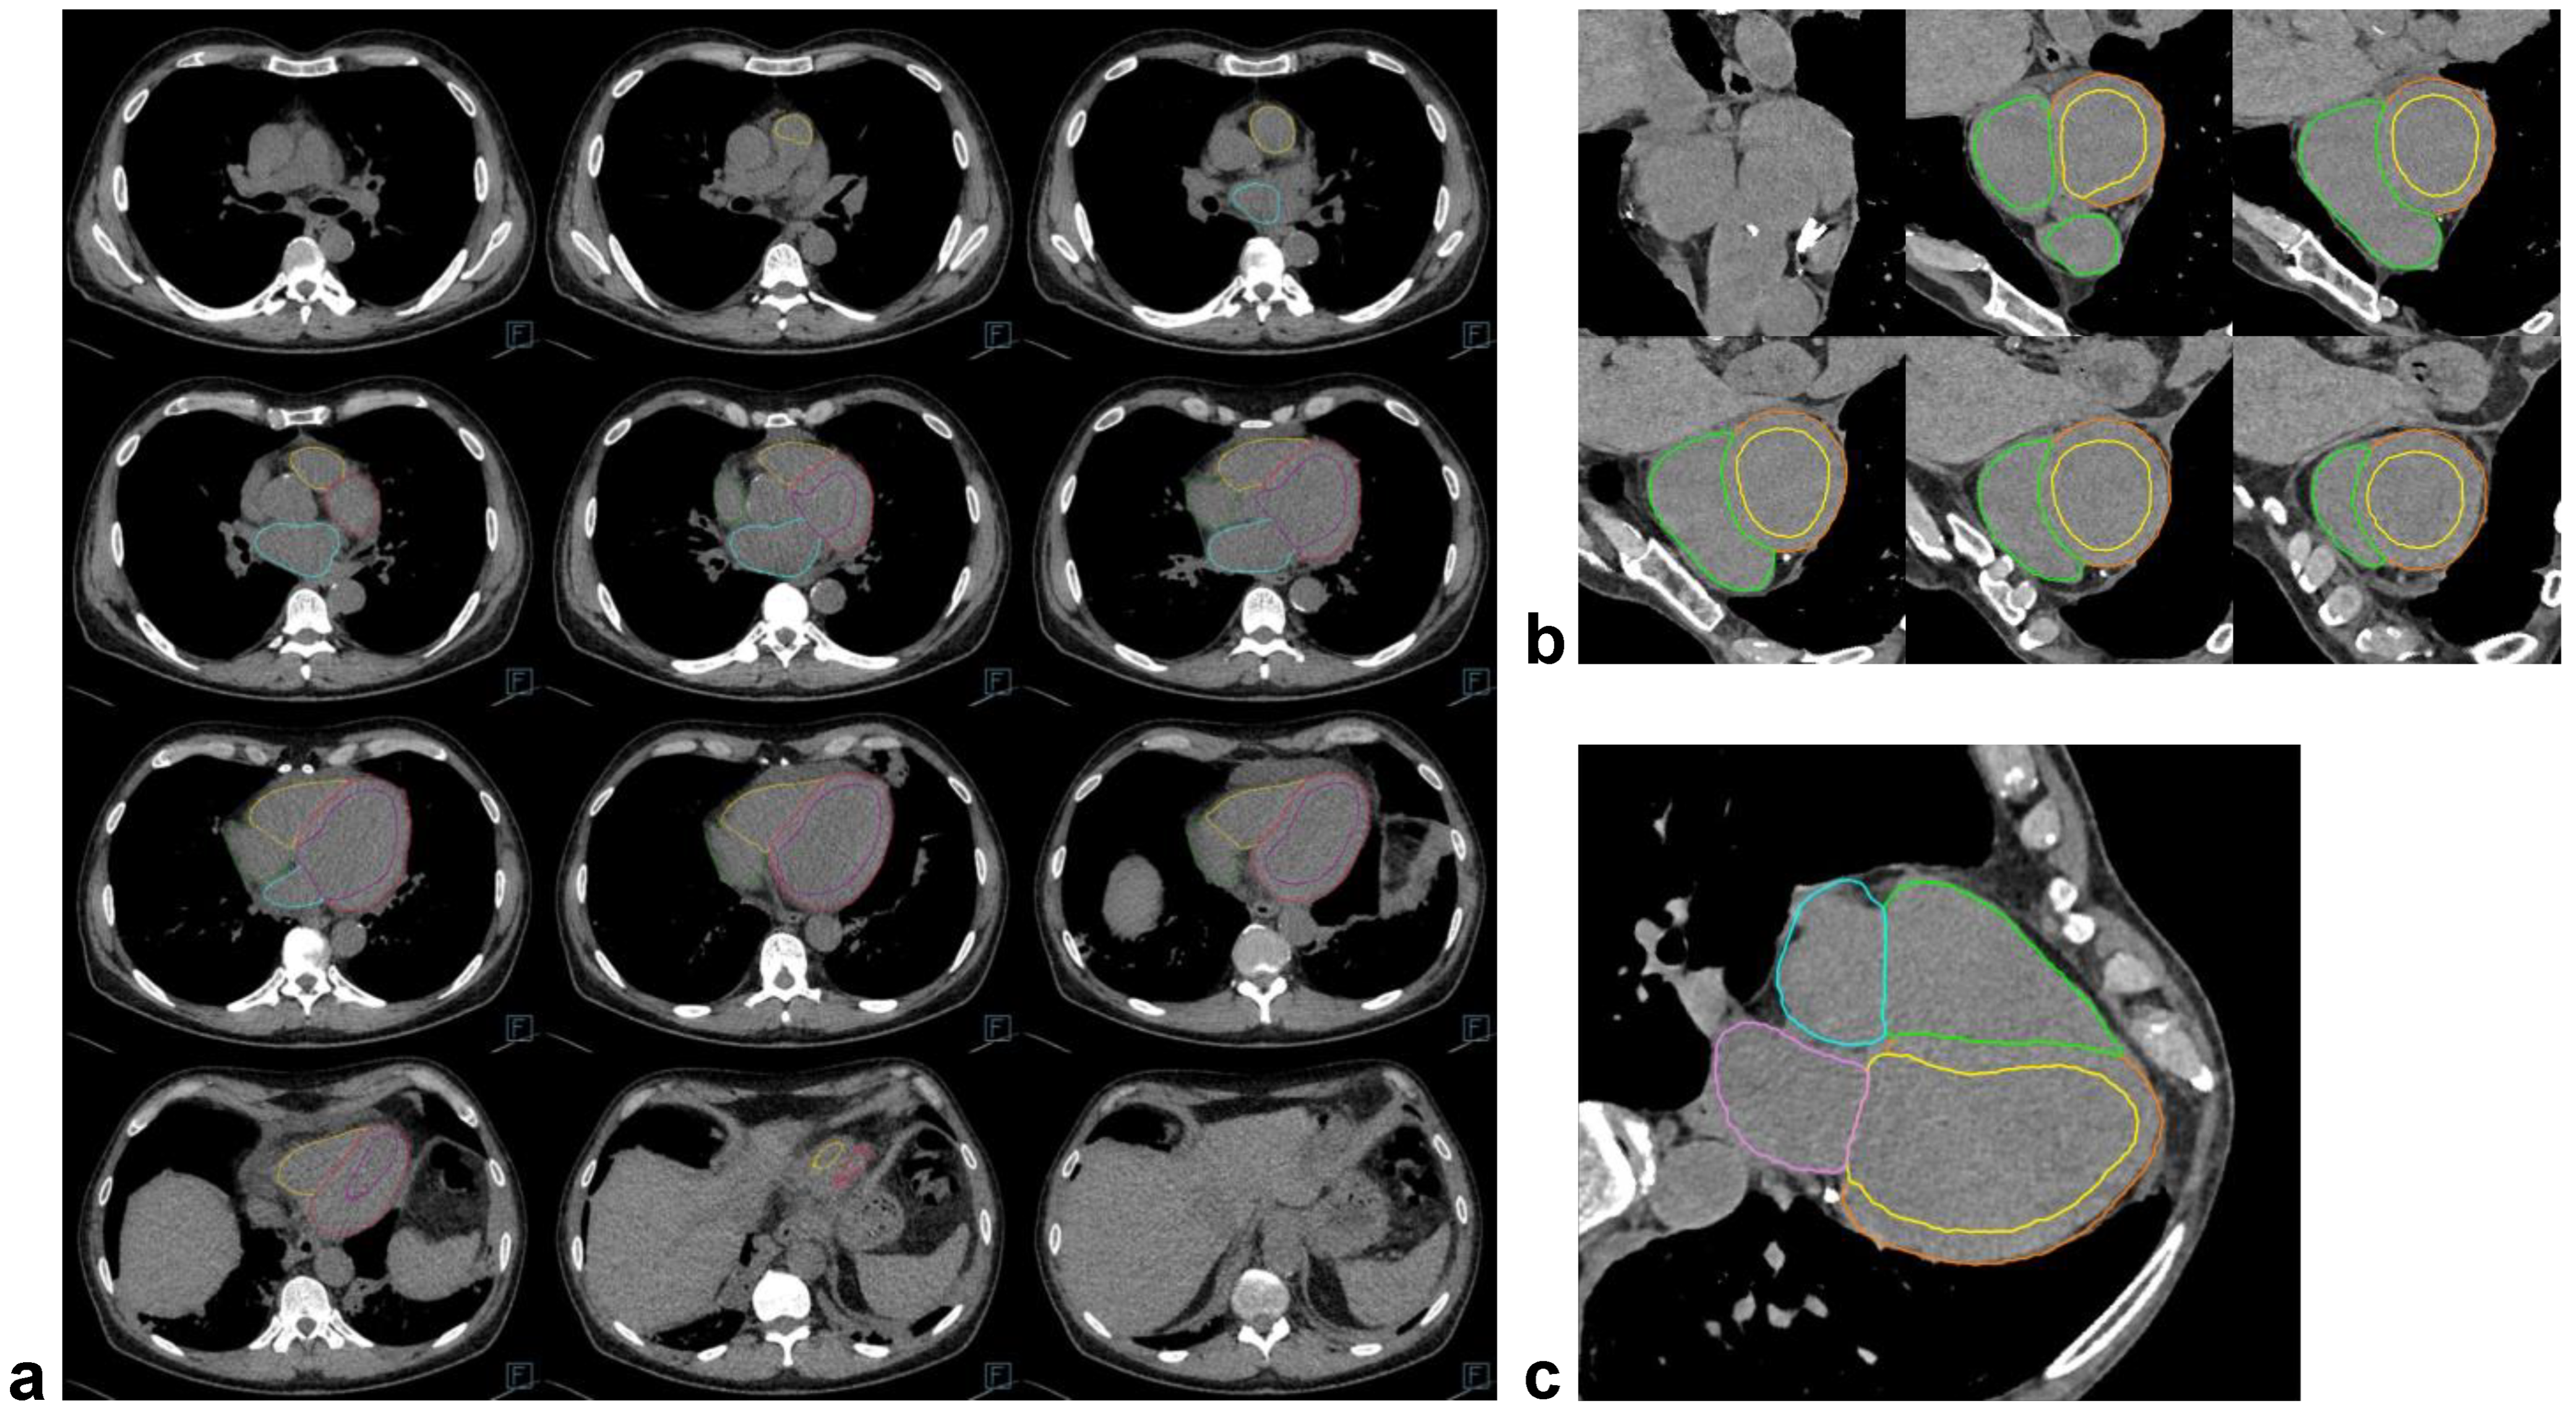

2.4. Non-Contrast Chest CT: Imaging and Fully Automatic Cardiac Segmentations

3.5. Visual Quality Assessment of the CT Segmentations